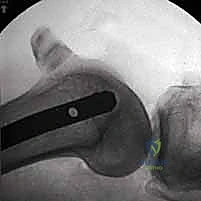

زراعة مفصل الرسغ الصناعي: حلول متطورة لآلام الرسغ المزمنة في صنعاء مع الأستاذ الدكتور محمد هطيف

اكتشف زراعة مفصل الرسغ الصناعي كحل فعال لآلام الرسغ المزمنة وتحسين الوظيفة. تعرف على الإجراء والتعافي مع خبرة الأستاذ الدكتور محمد هطيف في …